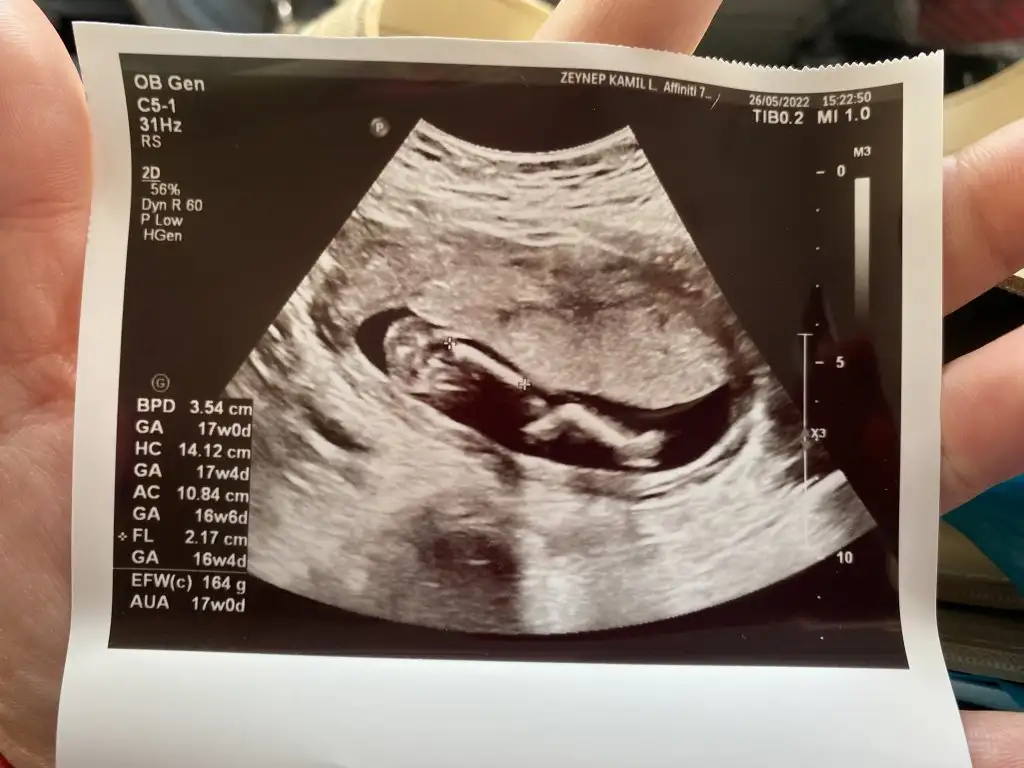

Merhaba 17+0 haftalık karından ultrason görüntüsü tahmin edebilir misiniz bizim minnak cinsiyetini hala saklıyor 🥰

Eklentiler

• 1D816C9A-C2AD-4C90-A49B-8217C6E7B3BE.webp

1D816C9A-C2AD-4C90-A49B-8217C6E7B3BE.webp

37,8 KB · Görüntüleme: 80